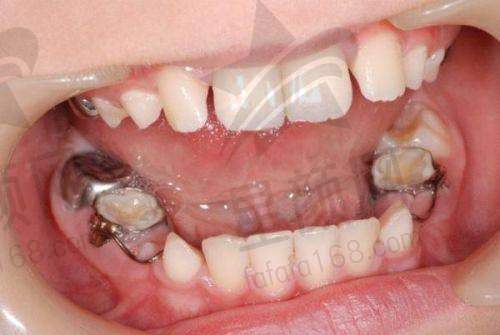

张女士的孩子牙齿排列不整齐,她一直担心孩子的牙齿问题会影响美观和健康。在朋友的推荐下,她带着孩子来到了深圳佳乐口腔诊所。医生为孩子进行了全方面的检查,并制定了个性化的牙齿矫正方案。在整个矫正过程中,医生和护士都非常关心孩子的感受,定期进行复查和调整。经过一段时间的矫正,孩子的牙齿逐渐变得整齐了。张女士对诊所的服务和治疗成效非常满意,她觉得在这里给孩子看牙特别放心。

深圳佳乐口腔诊所有好几位专精的牙医,他们不仅技术不错,而且态度非常好。在治疗过程中,医生会明确告诉患者治疗的项目,以及不同材料的收费情况。他们会如实描述各种材料的优缺点,给患者提供专精的建议,同时也会尊重患者的意愿,让患者自己做选择。这种不强制消费、不强制推荐贵材料的做法,赢得了患者的信任和好评。